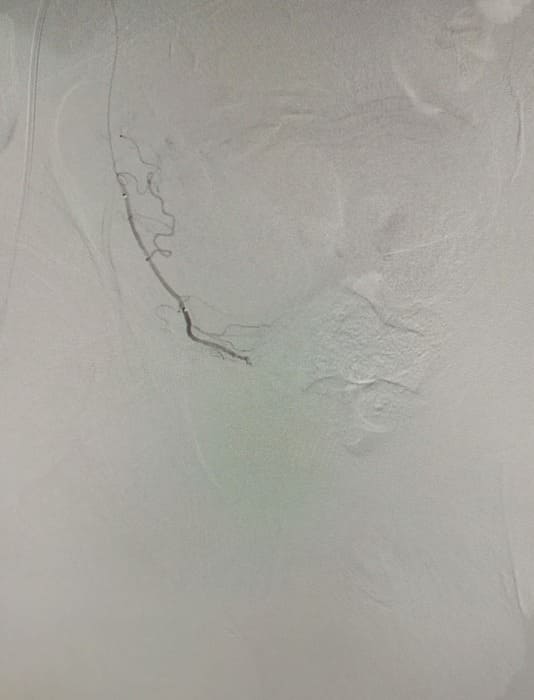

Зазвичай люди літнього віку мають вражені атеросклерозом та звивисті, внаслідок гіпертонічної хвороби судини. Цей випадок не був виключенням, тому нам довелося докласти максимум зусиль, використати високотехнологічне обладнання та інструменти, щоб віднайти цільові судини. На диво, незважаючи на попередню операцію, судинний малюнок рецидивної простати збігався з тим який буває у не оперованих пацієнтів. Тому нам вдалося їх чітко визначити з обох сторін та заповнити емболами. Це доволі кропітка праця, адже щоб викликати ішемію, необхідно поступово виключити кровоплин в усій тканині залози. Полегшувало операцію лише відсутність перетоків артерій на сусідні органи. Це дозволило нам безпечно емболізувати, не боячись негативних наслідків та ускладненнь.

Операція була виконана 28.05.2021. під місцевою анестезією, доступом через прокол в правій стегновій артерії. Вже на протязі тижня зменшилась кількість походів в туалет по маленькому (вночі до 1 разу), полегшилось сечовиділення та покращилось самопочуття хворого.